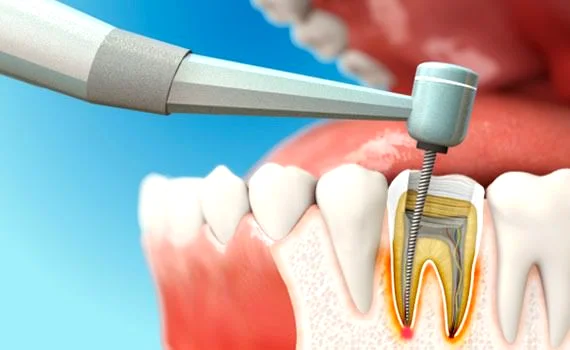

برای درک درد بعد از عصبکشی، ابتدا باید بدانیم در این درمان چه مراحلی طی میشود.

درمان ریشه یا عصبکشی زمانی انجام میشود که پالپ دندان (بافت نرم داخل دندان شامل عصب و عروق خونی) دچار التهاب یا عفونت شده باشد. در این فرآیند:

- عصب و بافت ملتهب از داخل کانالهای ریشه خارج میشود

- کانالها بهطور کامل شستشو و ضدعفونی میشوند

- فضای خالی با مواد مخصوص پر میشود

هرچند عصب دندان برداشته میشود، اما بافتهای اطراف ریشه (استخوان و لیگامانهای اطراف) همچنان زنده هستند و میتوانند به تحریک یا فشار واکنش نشان دهند.